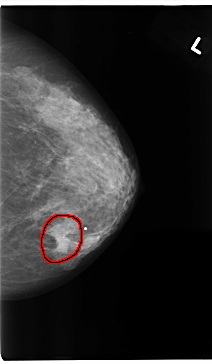

C_0175_1.LEFT_CC

LEFT_CC LINES 4728 PIXELS_PER_LINE 2752 BITS_PER_PIXEL 12 RESOLUTION 50 OVERLAY

FILE: C_0175_1.LEFT_CC.OVERLAY

TOTAL_ABNORMALITIES 1

ABNORMALITY 1

LESION_TYPE MASS SHAPE IRREGULAR MARGINS ILL_DEFINED

ASSESSMENT 5

SUBTLETY 4

PATHOLOGY MALIGNANT

TOTAL_OUTLINES 1

BOUNDARY